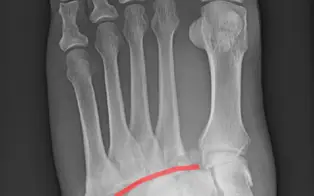

Entorse de Lisfranc